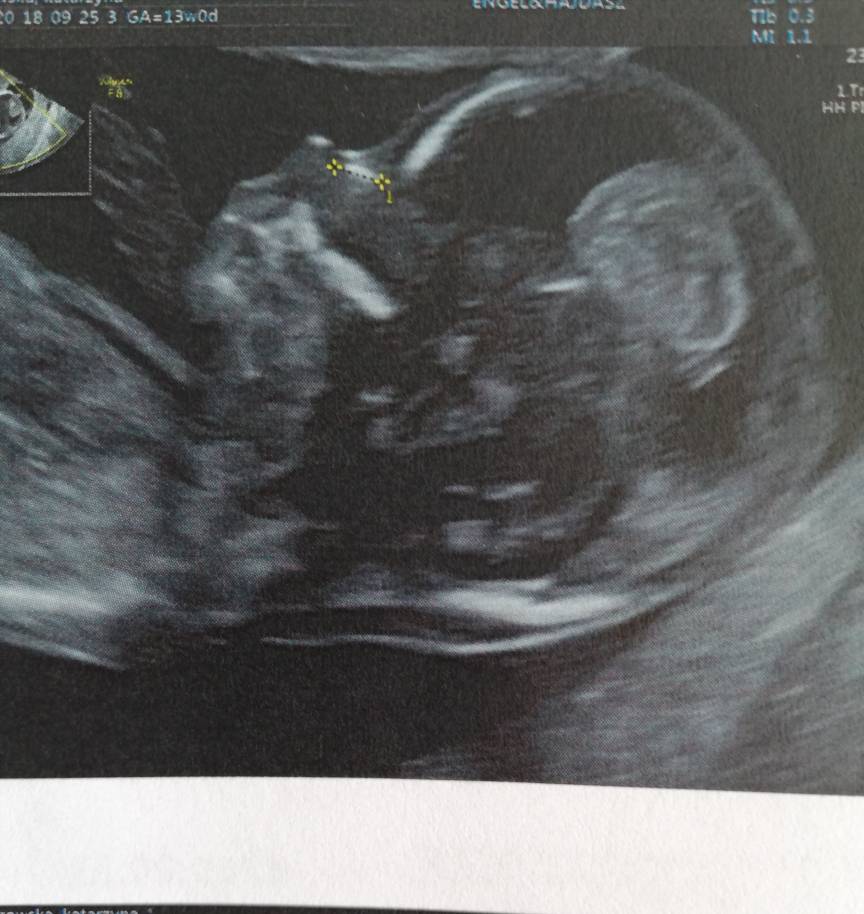

Cudne zdjęciaJa wczoraj byłam na prenatalnych ale po wizycie żeby uczcić poszłam na zakupy a wieoeczorem szybko padlam więc dzisiaj pisze dopieroDzidziuś ma już 6,61 cm tydzień ciąży identyczny jak z usg 13+0. Termin na 02.04. Wszystkie wymiary idealne, pięknie fikal dzidziuś

Wstępnie dr obstawia dziewczynkę ale jeszcze mamy się nie nastawiac. Trochę szok dla mnie bo byłam pewna że będzie drugi chłopczyk. Zobacz załącznik 901859Zobacz załącznik 901860Zobacz załącznik 901861Zobacz załącznik 901863